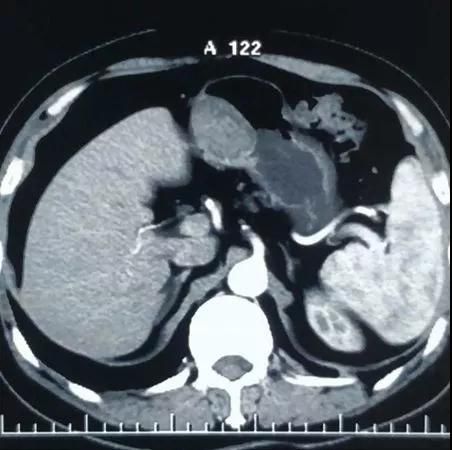

胃间质瘤是医学上的新词,是21世纪才正式命名和普遍使用的医学新名词。这种病变在胃镜下的形态学表现和我们常说的胃癌、胃淋巴瘤、胃息肉能直接区分开,因为它生长源于固有肌层,像土豆生长一样,可以通过超声内镜检查和CT检查确诊。